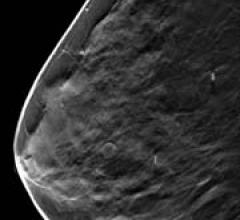

Despite decades of progress in breast imaging, one challenge continues to test even the most skilled radiologists ...

September 26, 2011 — Hoag Breast Care Center recently became the first breast care center in California and one of a handful in the United States offering 3-D digital breast tomosynthesis for breast cancer screenings. The technology promises to improve breast cancer detection, especially in young women and women with radiographically dense breast tissue.